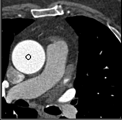

Samples for ascending aorta detection (black circle):

Cluster of candidate points in the ascending aorta.